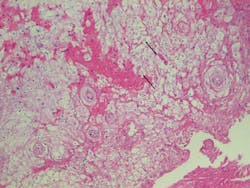

When viewed microscopically, the tissue exhibits acanthosis or a heavy thickening of the prickle cell layer of the epithelium. This promotes the thick white appearance that is very characteristic of WSN. Another feature noted is the cytoplasmic clearing of the epithelial cells that a pathologist will recognize.